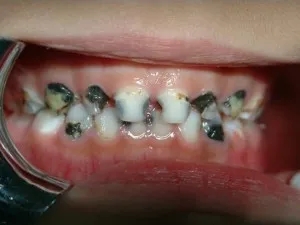

严重“奶瓶龋”患者,真实的口腔照

还没等乳牙长齐,已长出的乳牙就变黑了

常见于上排门牙靠近嘴唇面

及牙齿与牙齿相邻面出现大面积的龋坏

这种现象大都是“奶瓶龋”所致